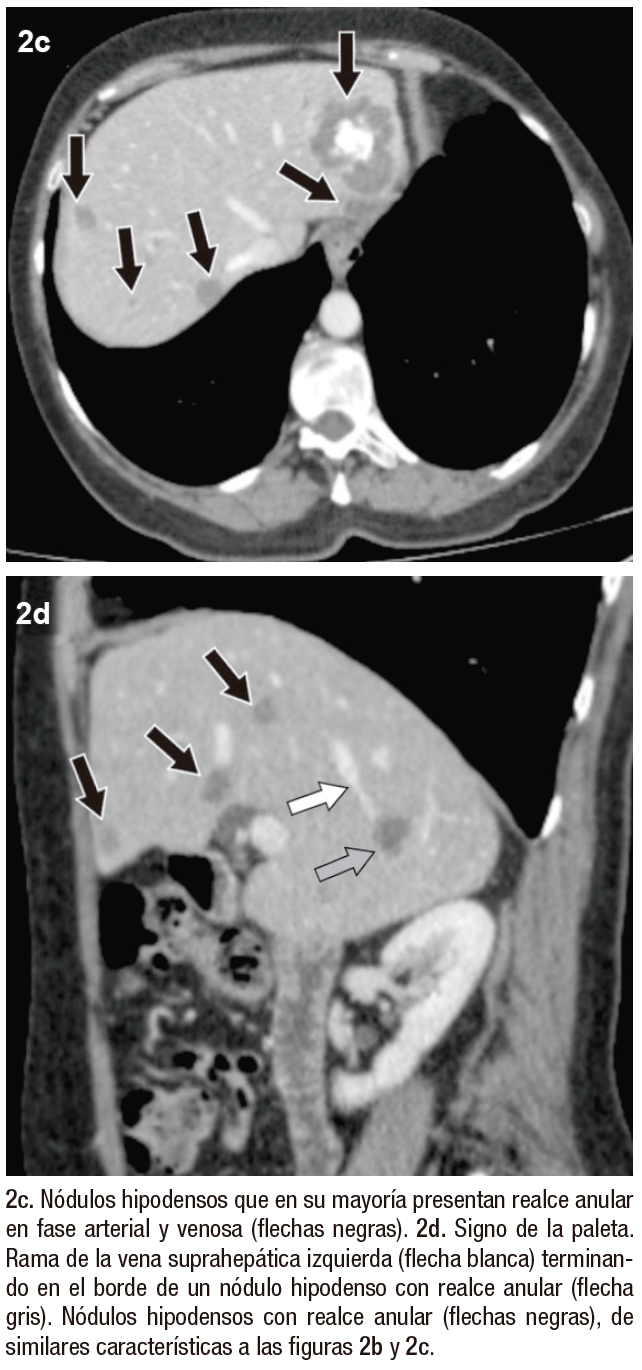

Posteriormente, se realiza una ecografía abdominal en la que se muestran innumerables nódulos hipoecogénicos, de márgenes parcialmente circunscritos, con calcificaciones en su interior, algunos causantes de retracción capsular, sin evidencia de flujo vascular con Doppler color (Figura 1). Tras estos hallazgos, se continúa la valoración mediante TCMD (Tomografía Computada Multi detector) con contraste endovenoso, donde se observan, en consonancia con la ecografía, numerosos nódulos isodensos e hipodensos, con realce en anillo en fases arterial y venosa, distribuidos en ambos lóbulos hepáticos.

En el lóbulo izquierdo se destaca un nódulo dominante, acompañado de groseras calcificaciones internas, que mide 48x42x39 mm (Figura 2).

Figura 2. TCMD hepática en corte axial, sin contraste (2a) y con contraste endovenoso (2b-d). Fase arterial (b)

Figura 2. 2c y 2d) Fase venosa